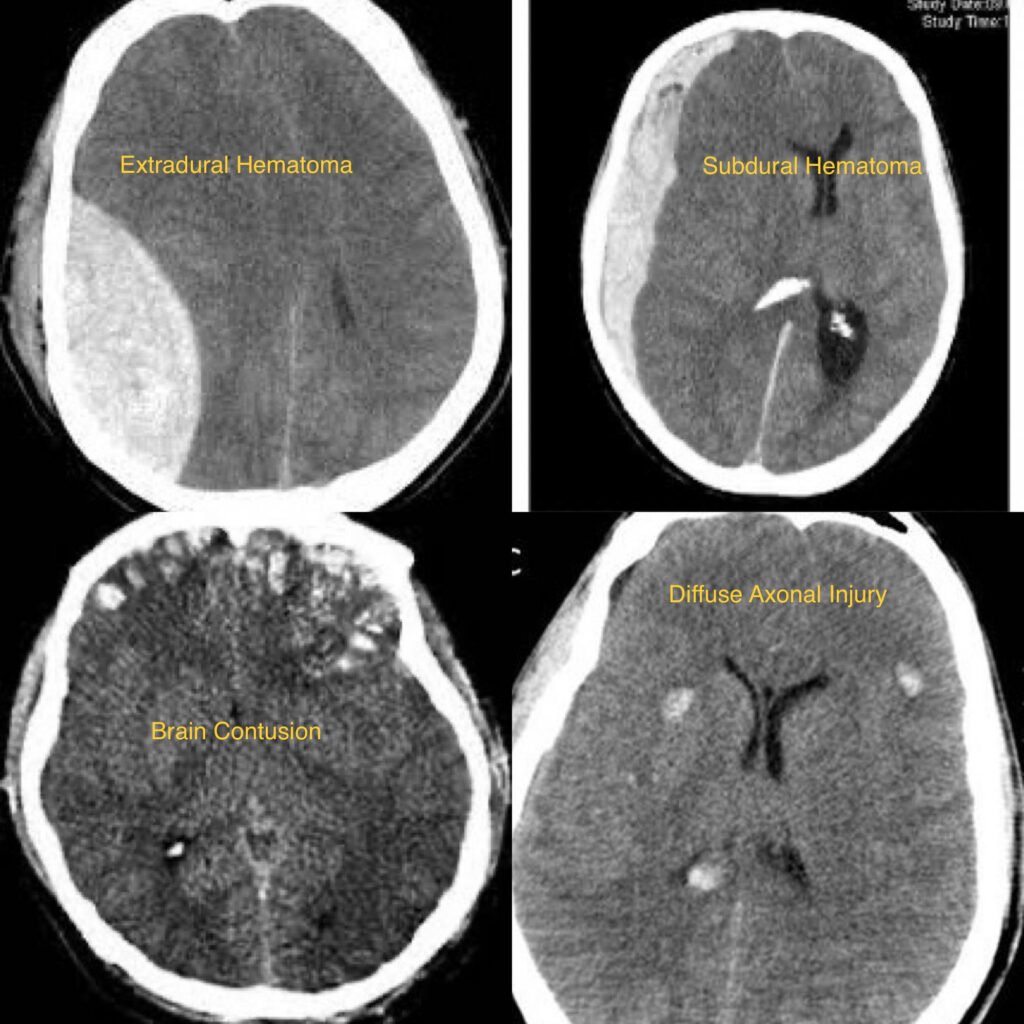

- Diagnosis typically involves a thorough neurological examination, assessment of symptoms, and imaging studies such as CT scans or MRI to evaluate the extent of brain injury.